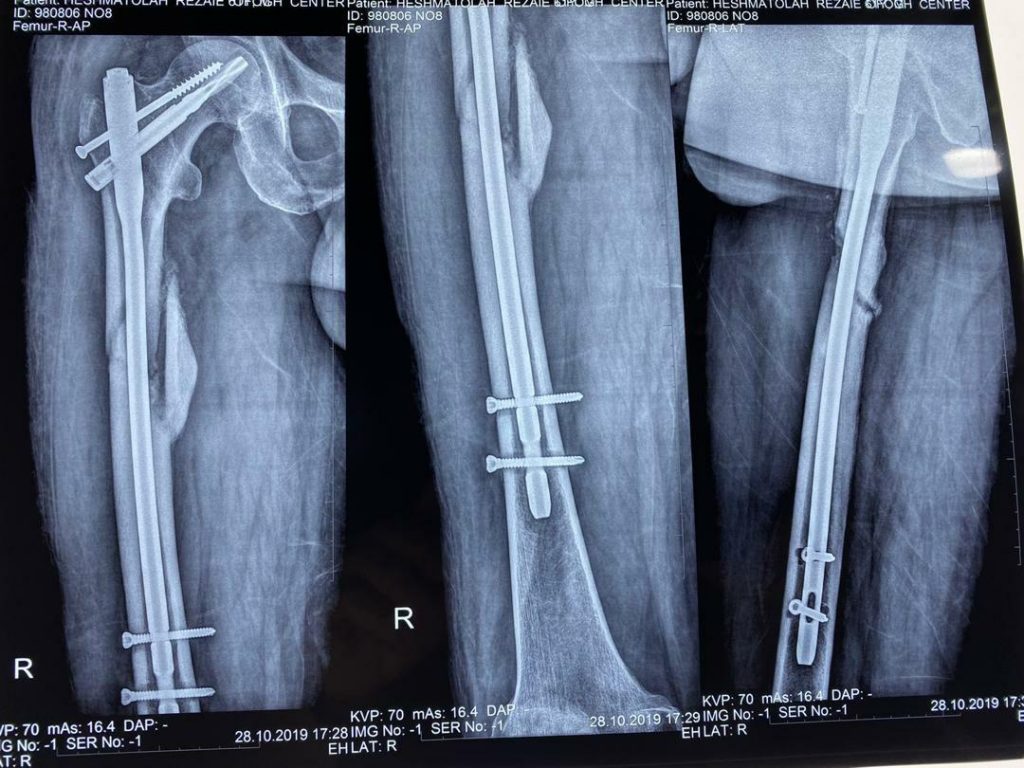

جراح ارتوپدی و شکستگی

3. شکستگی و دررفتگی استخوان

درصورتی که شدت آسیب وارد شده به مفصل به گونه‌ای باشد که با سایر روش‌های درمانی آسیب برطرف نشود، جراح ارتوپد عمل تعویض مفصل را برای درمان توصیه می‌کند. با این عمل، بخشی یا همه محل آسیب دیده مفصل با پروتز جایگزین می‌شود. عمل تعویض مفصل به طرز قابل توجهی درد مفاصل آسیب دیده را کاهش می‌دهد، موجب بهبود توانایی حرکتی مفصل و کاهش مشکلات حرکتی فرد و به طور کلی باعث بهبود کیفیت زندگی فرد می‌شود.

انواع عمل جراحی‌ تعویض مفصل یا آرتروپلاستی، با توجه به نوع مفصل عبارتند از: عمل تعویض مفصل زانو، عمل تعویض مفصل لگن و ران، عمل تعویض مفصل شانه، عمل تعویض مفصل آرنج و عمل تعویض مفصل مچ پا.